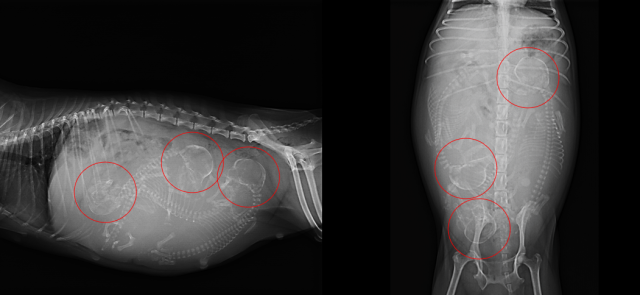

事前にレントゲン検査を行い、お腹の中の胎子の数を確認します。

🔴赤丸が胎子の頭を示しています。今回は3頭の胎子が確認できました。